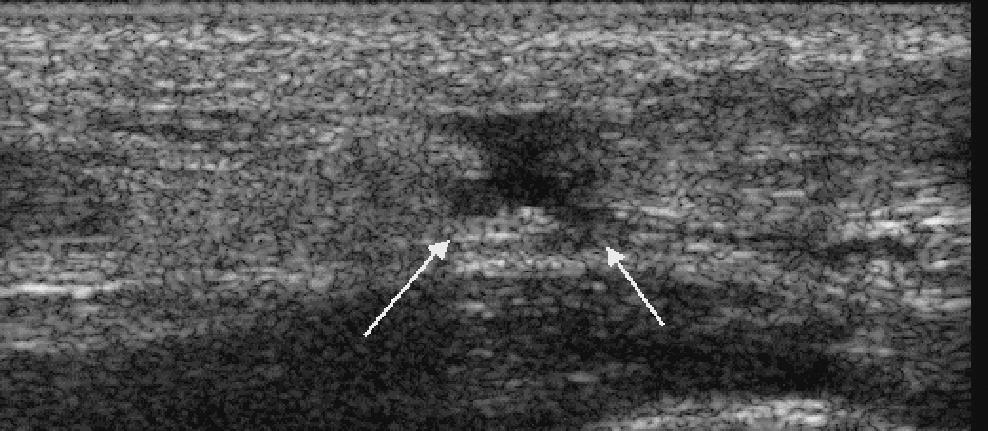

跟腱断裂声像图